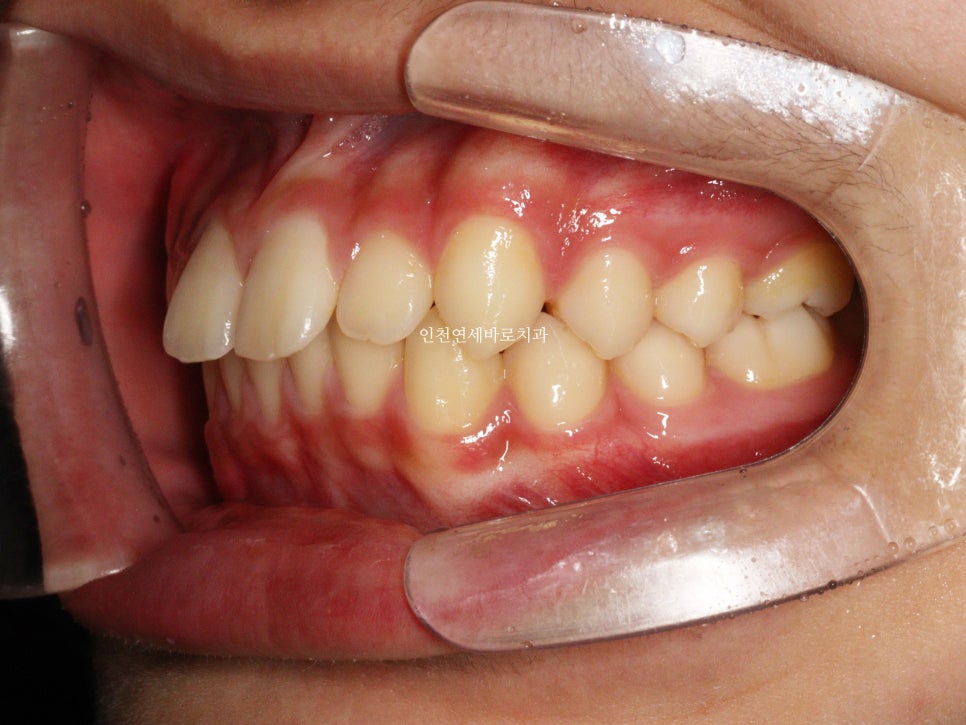

치료 전과 후 입니다.

앞니가 후방이동 한것이 확인됩니다.

우리는 부분교정을 한것이 아니라 간단한 전체교정을 한것입니다.